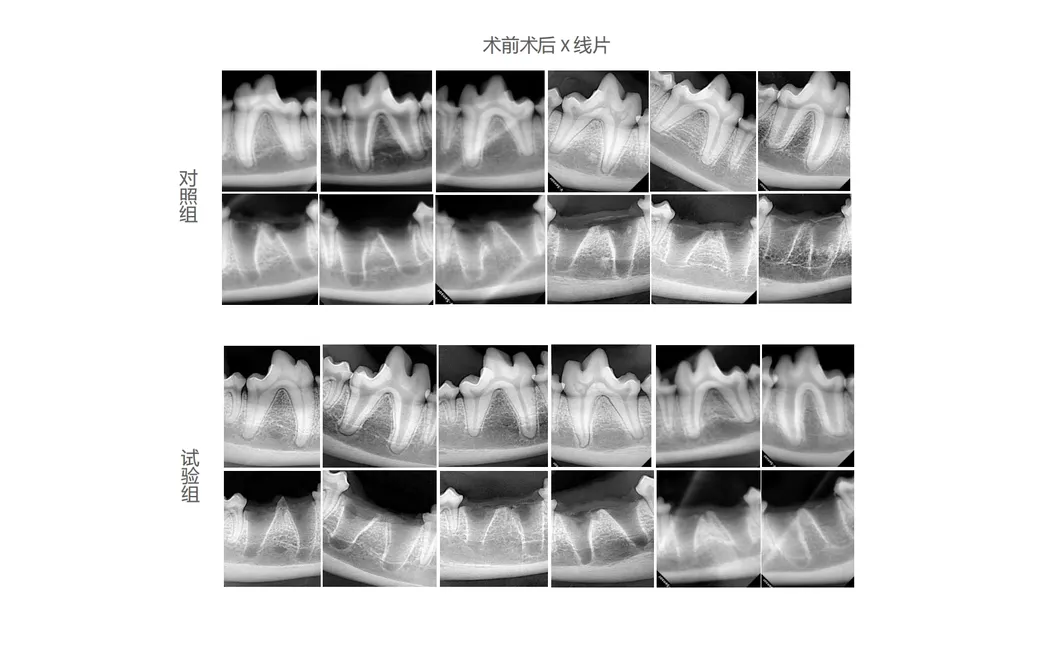

Experimental Content

In this study, dogs were chosen as subjects to assess the effectiveness of advanced dental tools. The control group used traditional manual devices, while the treatment group utilized the state-of-the-art Pneumatic Dental Elevator Kit. Researchers documented physiological parameters, complication incidence, extraction duration, and socket damage. The study also evaluated soft tissue healing, haematological data, and histological assessments.

Experimental Results